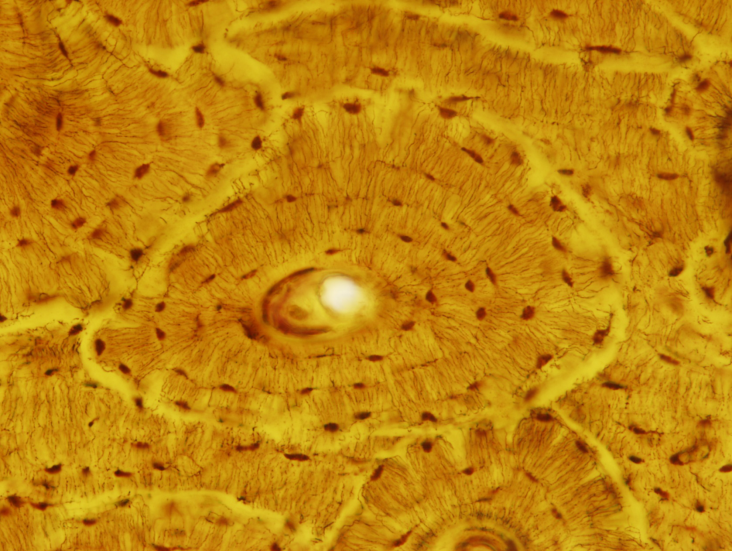

哈弗斯系统光镜像: